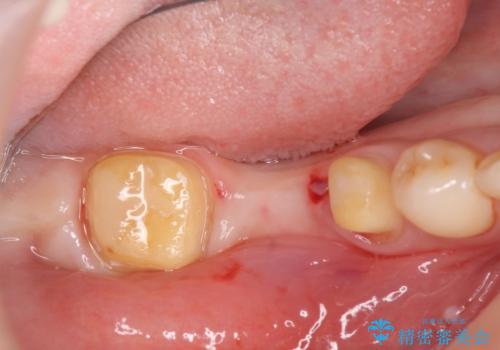

- 上下1本づつの歯を失い、噛めないことの改善を求めて来院されました。

保存可能な歯の虫歯・根管治療を行い、喪失した部分はインプラントを埋入、オールセラミックジルコニアクラウンを製作し審美的に仕上げていきます。

今回下顎の欠損部位はブリッジも検討されましたが、並行性の観点から最後方臼歯の神経を取るリスクを抑えるためインプラント治療を選択しました。